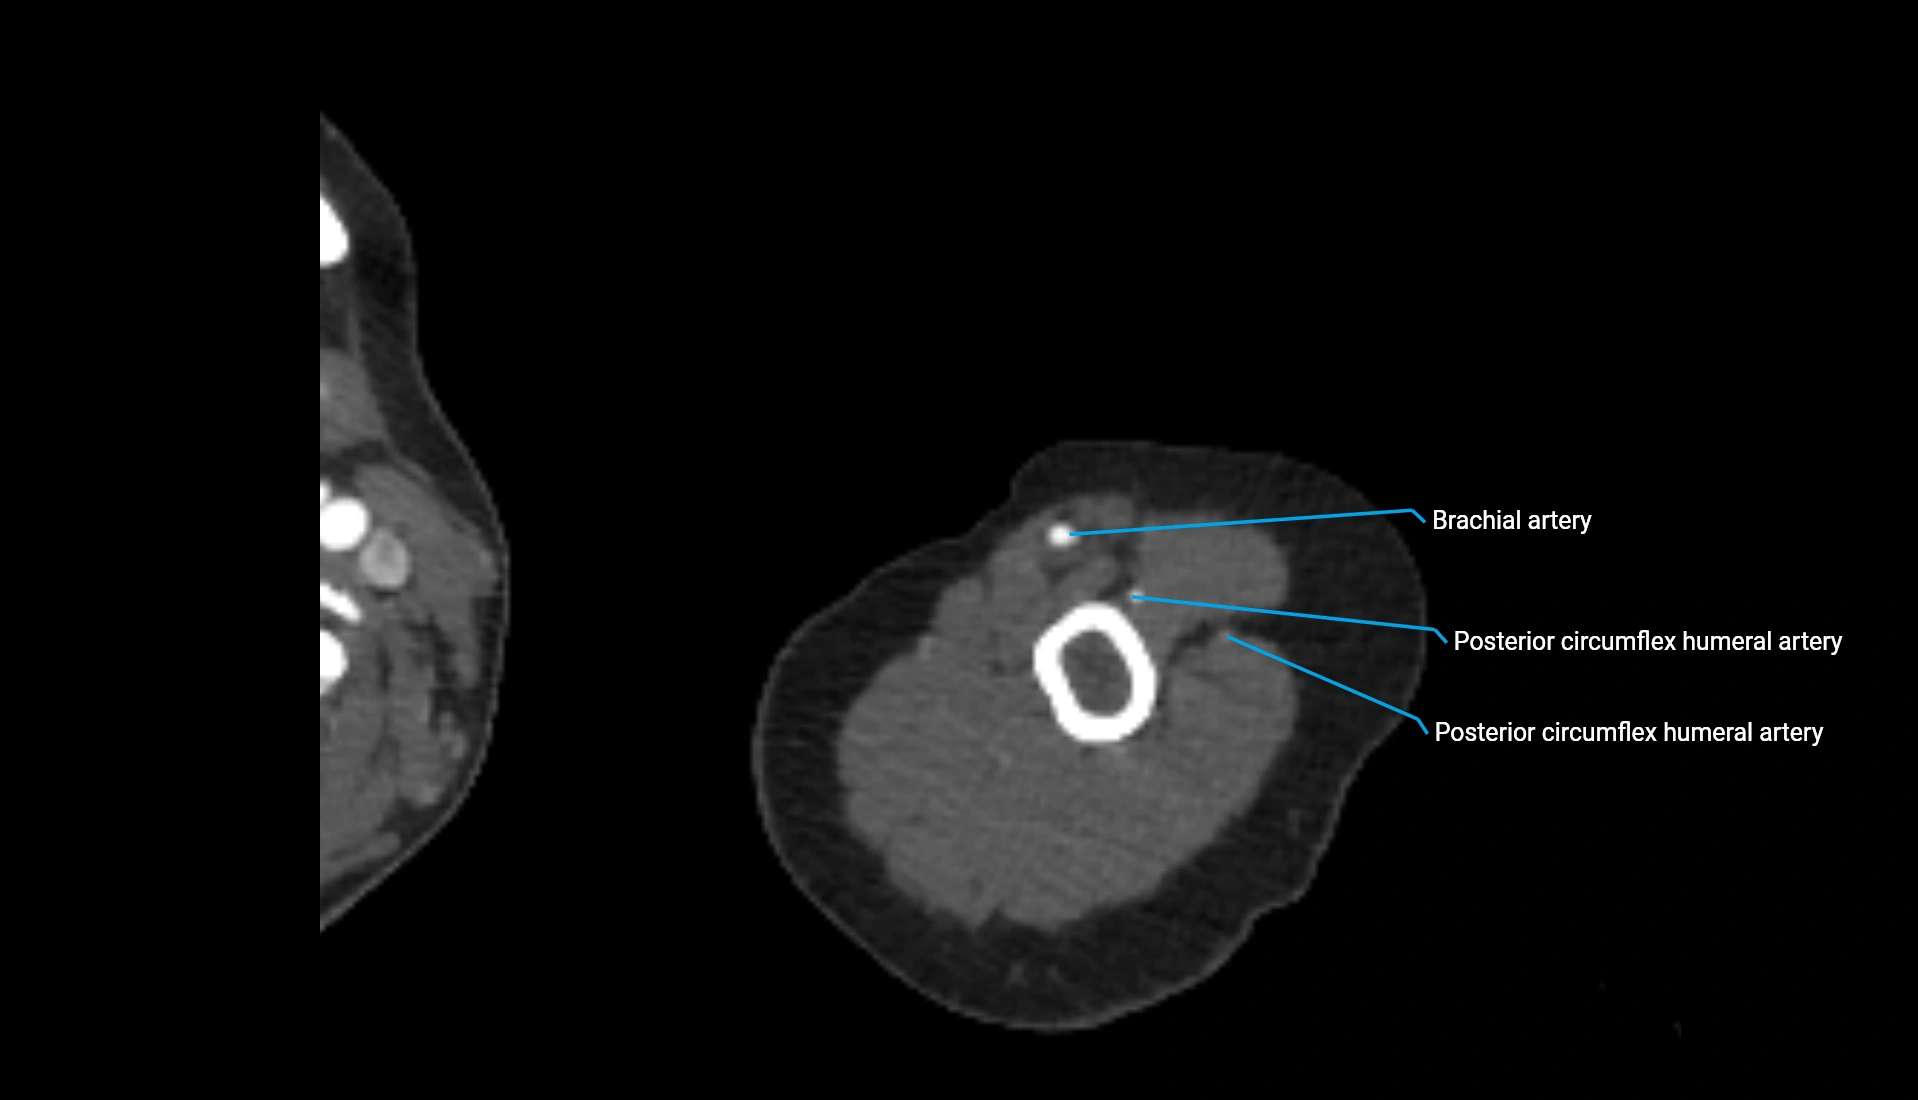

CT Appearance

Non-Contrast CT:

• Cortex: High-density, sharply defined

• Subchondral bone: Dense cancellous matrix

• Articular surface: Smooth concave contour articulating with the capitellum

• Excellent for evaluating bone integrity, alignment, and subtle fractures